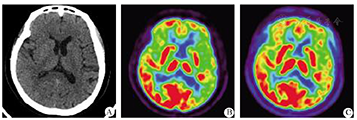

患者2女,57岁,受教育2年。因"发现记忆力下降1年伴命名障碍7月余"于2015年9月求治于首都医科大学宣武医院神经内科。患者表现为隐袭起病。2014年其丈夫发现患者近期记忆下降,远期记忆较好。2015年起患者语言功能障碍较为突出,说话缓慢而流畅,命名障碍,如买菜时知道要买黄瓜,但是叫不出"黄瓜";知道茶杯是用于喝水,但说不出"茶杯"。患者交流困难,常常答非所问。曾先后在数家医院神经内科就诊,但因患者无法进行病史询问而放弃就医。患者日常生活能自理,人格、行为无异常。患者既往高血压、血脂异常1年,未规律服药,否认其他特殊病史。体检:生命体征平稳,内科系统查体无异常。专科检查:患者意识清楚,精神稍差,构音清,语言障碍突出,找词困难、命名性失语,说话慢而流畅;可以书写自己的名字,书写4位数的年份"2015"时不完整,最后那个"5"不能写出来;记忆力下降,计算力下降,空间定向力差,时间定向力可。颅神经检查未见异常,四肢肌张力正常,四肢肌力V级、感觉对称、反射适中,共济运动稳/准,病理征未引出。生化检查:(1)载脂蛋白E(apolipoprotein E, APOE)基因:APOE-ε3/4;(2)生化10项+同型半胱氨酸:葡萄糖9.24 mmol/L(正常范围3.9~6.1),甘油三酯3.05 mmol/L(正常范围0.45~2.25),总胆固醇7.28 mmol/L(正常范围3.24~5.7);低密度脂蛋白5.32 mmol/L(正常范围2.08~ 3.12);(3)血常规:嗜碱性细胞2%(正常范围0~1),红细胞平均体积80.9(正常范围82~95),白细胞计数3.62×109/L(正常范围4~10),淋巴细胞计数0.67×109/L(正常范围1~3.3);(4)梅毒螺旋体特异性抗体:阴性;(5)凝血4项:未见异常;(6)甲功:促甲状腺激素9.02 mmol/L(正常范围0.34~5.6),甲状腺球蛋白抗体1226.59 mmol/L(正常范围0~4);(7)维生素B12+叶酸:未见异常。神经心理学检查:(1)MMSE不能完成;(2)MoCA不能完成;(3)AVLT不能完成;(4)日常生活能力:22分;(5)临床痴呆评定量表:0.5分;(6)改良的Hachinski缺血评分不能完成,汉密尔顿焦虑量表及汉密尔顿抑郁量表均不能完成。影像检查:PET-CT检查结果示左侧大脑半球萎缩、低代谢、低灌注,以颞叶为甚(图1)。

A:左侧大脑半球萎缩;B:左侧大脑半球低代谢;C:左侧大脑半球低灌注,以颞叶为甚

2例患者均为老年女性,发病年龄57、66岁。2例患者均无明确脑卒中史及脑外伤史,临床表现均为突出的语言功能障碍。2例均有影像学资料,第1例患者T2FLAIR像显示左侧颞叶明显萎缩;第2例患者PET-CT像显示左侧大脑半球萎缩、低代谢、低灌注,以颞叶为甚。第1例患者家属拒绝治疗,第2例应用卡巴拉汀加用舍曲林等治疗。2015年10月20日电话随访,第2例患者精神、睡眠改善,话语增多,语言障碍无明显改善。